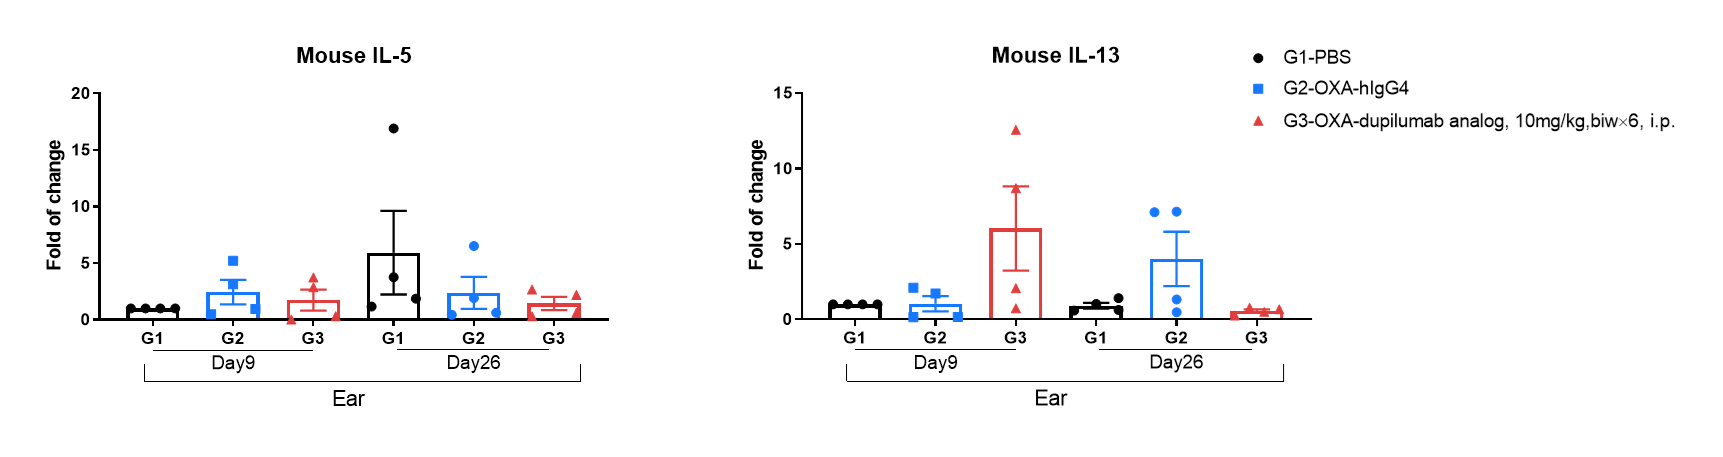

Mouse IL-5 and IL-13 expression analysis in OXA-induced AD model of B-hIL4/hIL4RA mice by RT-qPCR. Ear was collected at day 9 and 26 and total RNA of these samples were extracted. Then RNA samples were reverse transcribed and mouse IL-5, mouse IL-13 levels were measured by RT-qPCR.